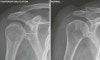

X-ray : 어깨 후방 탈구(Posterior shoulder dislocation)

영상 검사

AP view에서는 팔이 내회전 상태로 인해 상완골 근위부가 백열 전구처럼 보이는 소견(light bulb sign)을 제외하면 정상 소견을 보여 오진되는 경우가 종종 있습니다.

Lateral view나 axillary view에서 상완 골두의 후방 탈구를 관찰할 수 있습니다.